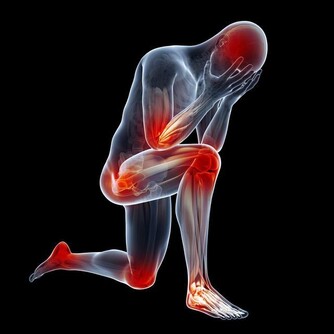

【早安健康/周舒涵編譯】每天下班 回到家,常會覺得肩膀硬硬卡卡的嗎?這時候如果有人可以幫忙按摩肩膀,那將會是多棒的享受!但是只有自己一個人也沒關係,今天就要告訴你,比起「按」肩 膀,「捏」肩膀才是正確解除僵硬的方法,最棒的是,「捏」肩膀只要自己一個人就可以輕鬆實行。 血液循環不良造成肩膀酸痛,「按」或「槌」都只能帶來暫時性的放鬆 肩膀酸痛的成因,其實就是肩部血液循環不良,相較於歐美人種,亞洲人骨架較小,頭部重量帶給肩膀的壓力也比較大。或許你也以為肩膀酸痛是上了年紀才會有的問題,現在它卻越來越年輕化,就連小學生都可能因為長時間維持同一姿勢,而提早出現肩膀酸痛的問題。 也有許多人認為,肩膀酸痛是因為肌肉僵化所造成。雖然肩膀肌肉缺乏運動,的確可能使其失去柔軟性,但卻不是肩膀酸痛的主因。許多人在肩膀酸痛時總會下意識地「按」肩膀、「槌」肩膀,這麼做其實只能暫時放鬆肩部而已,無法根本解決肩膀酸痛問題。 肩膀怎麼越「按」越酸?其實「按」肩膀會使原本柔軟的肌肉變僵硬 你有發現嗎?我們「按」完肩膀之後,經常又想要繼續「按」肩膀,這是因為隨著按摩方式不同,對肩膀也會產生不同的作用,而這些作用甚至可能是負面作用! 「按」肩膀之所以可能會產生負面作用,是因為肌肉細胞的狀態各異所造成,同一片肌肉組織里,可能有收縮僵硬的肌肉,也可能有鬆弛柔軟的肌肉,若一視同仁以「按」的方式給予刺激,僵硬的肌肉固然暫時獲得放鬆,原本柔軟的肌肉卻會因為刺激而變得容易僵硬。 「按」肩膀增負擔、「槌」肩膀效率差,「捏」肩膀才正確! 相較於「按」肩膀可能增加肩膀的負擔,「槌」肩膀反而好一些,但「槌」肩膀又只有槌到的地方才有效,似乎太沒有效率了。接下來就要介紹正確的按摩方法,想要解決肩膀酸痛問題,原來只要自己捏捏肩膀就可以了。 自己「捏」肩膀! 步驟